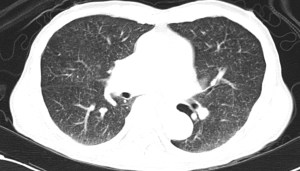

His chest X-ray and a representative cut from the CT thorax is shown below.

The CT (it’s much harder to appreciate on the chest X-ray) shows “millet-like” nodules over the lung fields. The second sputum specimen sent was positive for acid-fast bacilli on microscopy, and both sputum samples grew Mycobacterium tuberculosis. This man had miliary tuberculosis, so termed because of the appearance of the many tiny lung nodules on histology. Although the risk of mortality is higher than “ordinary” pulmonary tuberculosis, treatment is the same.